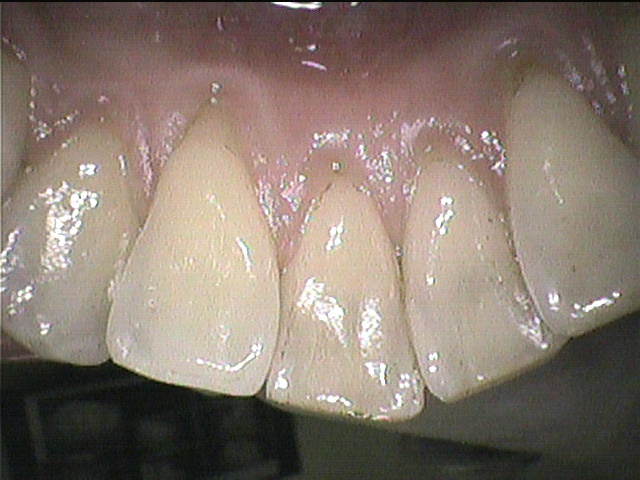

クリーニング前

半年に一度くらいの頻度で定期的にクリーニングに来てくださっている患者さんです。

綺麗に磨けていて、歯垢や歯石はそれほど多くなく